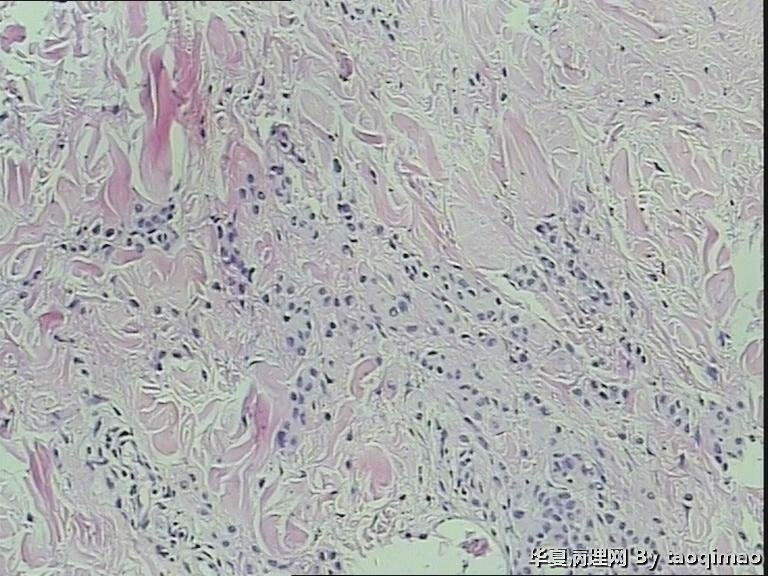

两例头皮肿物有差别么

这个患者女,24岁,右颞部头皮肿物 24年,带皮的组织一块1.7x1x1,突出于皮肤表面,灰白色肿物,剖面实性灰白,请各位老师给帮忙诊断一下,这两个病例是同一个诊断么

第一:皮内痣 第二:皮内痣并表皮囊肿

头皮皮内痣常呈皮赘样,质软有蒂,很多时候退化后呈正常肤色,切片中常有成熟的脂肪细胞,临床很容易误诊,诊断皮内痣应该没有问题的!

第二例合并的有个小的表皮样囊肿,或说粟丘疹。

灰白色,我想是由于有的皮内痣本身没有太多色素吧,不少皮内痣是皮色的。你的俩病例,片子里都没啥见到色素,应该可以解释了吧。